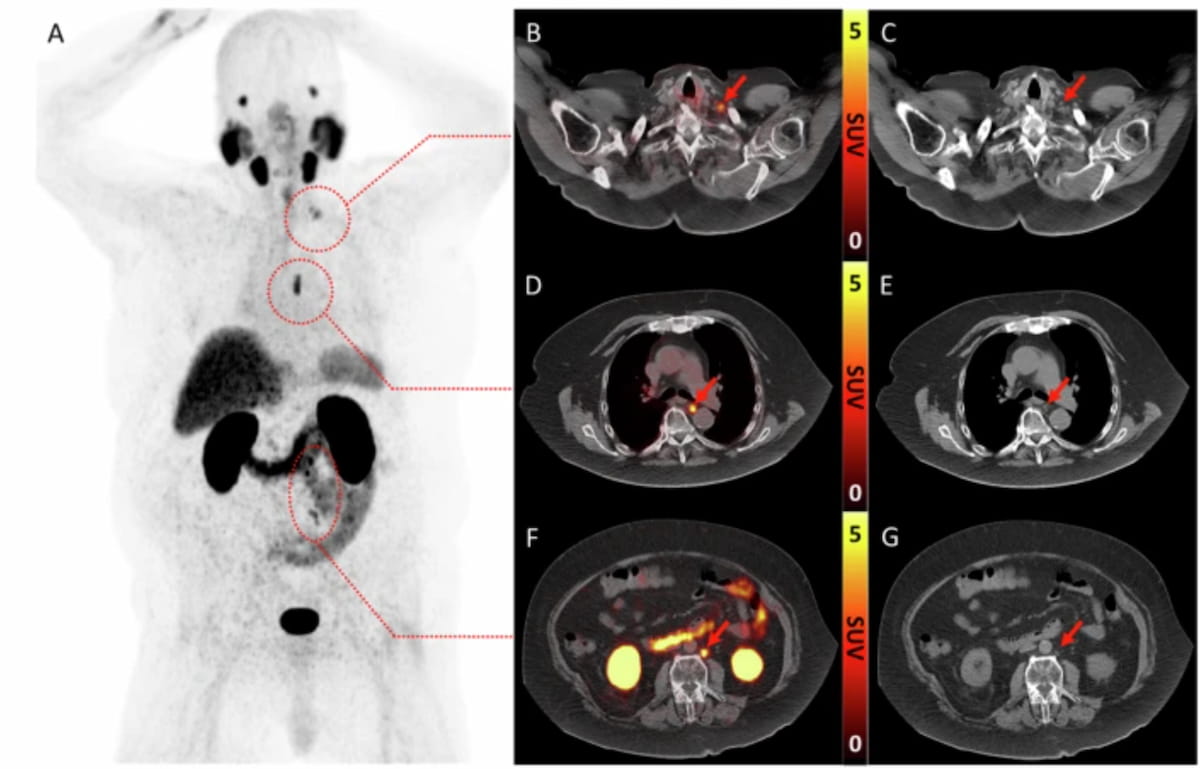

Offering current perspectives on the use of prostate-specific membrane antigen (PSMA) positron emission tomography (PET) and magnetic resonance imaging (MRI) in patients with advanced prostate cancer (PCa), the Prostate MRI Working Group of the…

Nine Takeaways from New Review of PSMA PET/CT and Whole-Body MRI for Advanced Prostate Cancer